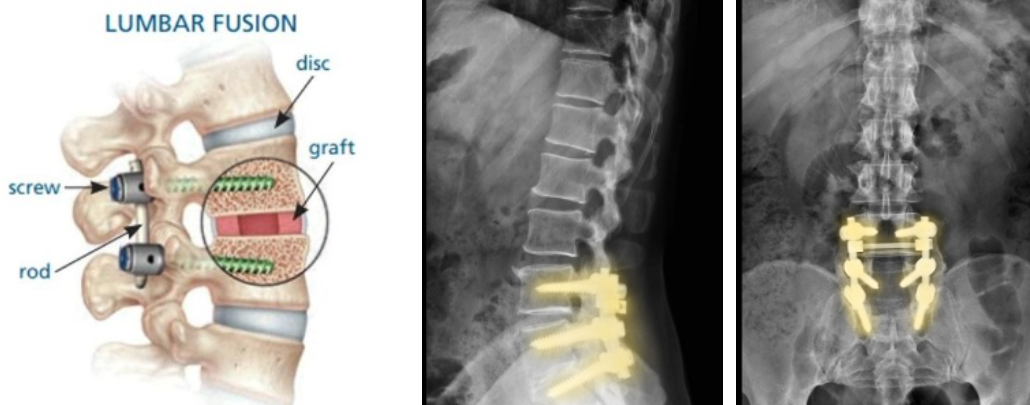

3. 척추 유합술 Spinal fusion

- 척추 유합술(나사못 고정술, Spinal fusion) : 신경을 압박하는 디스크를 제거하고 인공뼈 등을 삽입하여 유합하거나 불안정한 척추 마디를 고정하여 척추의 안정성을 확보하는 수술입니다.